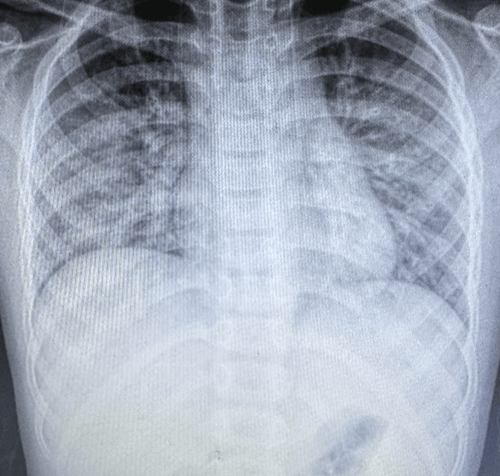

胸部X线检查(图1)显示双侧弥漫性阴影,下肺叶更明显,提示

(图1 胸部X线检查)